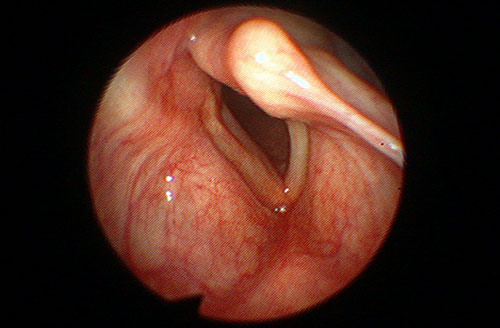

Paraliza jedne glasnice zbog pritiska tumora jednjaka na živac koji okreće glasnicu